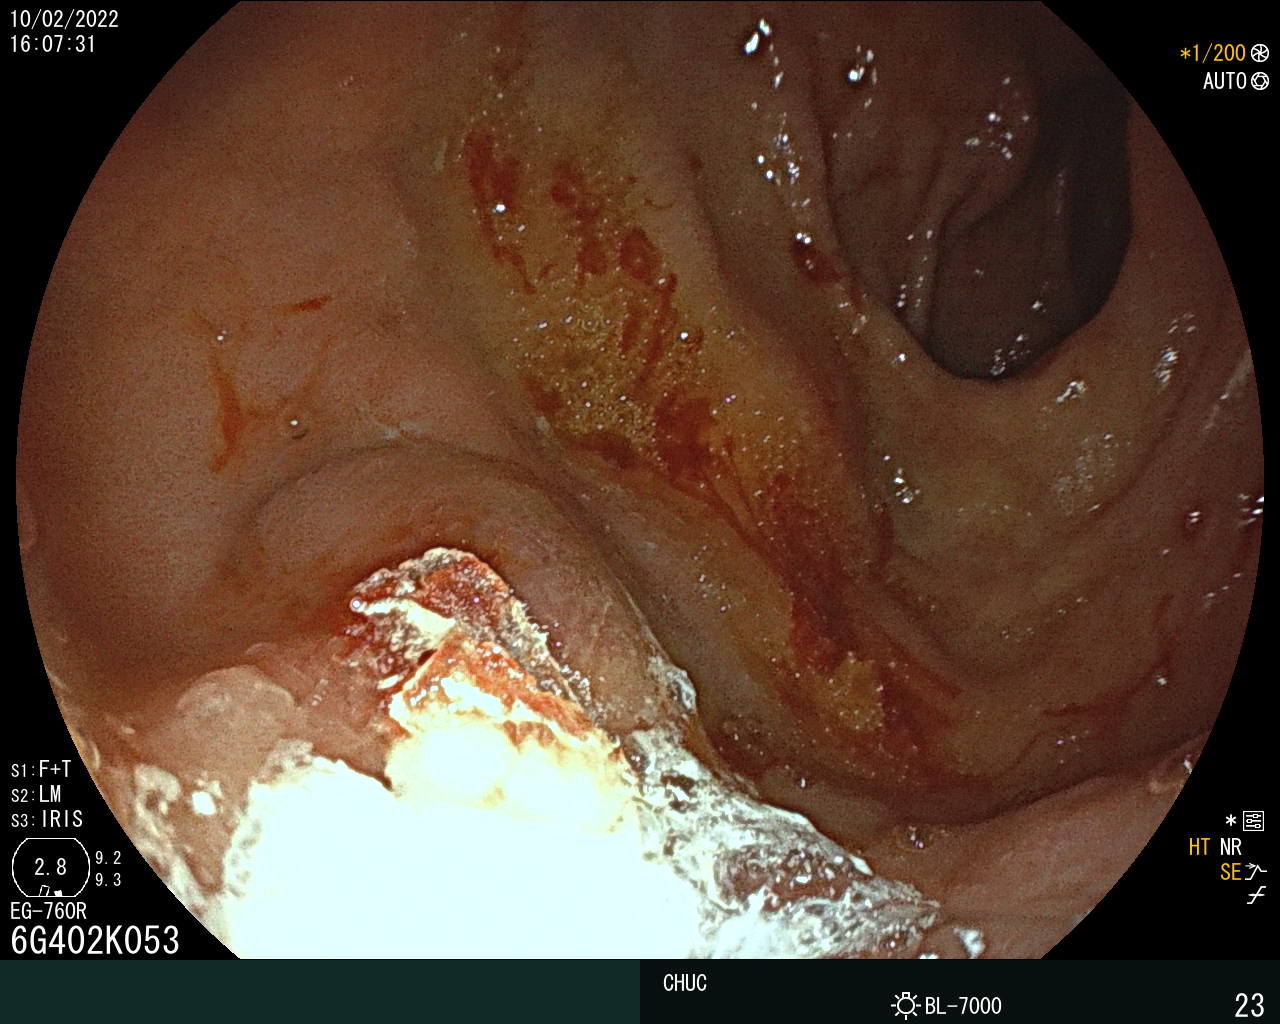

Duodenal varix as a presentation of hepatocellular carcinoma

André Coimbra Trigo, Mafalda João, Sandra Lopes, Pedro Figueiredo

Centro Hospitalar da Universidade de Coimbra

A 79-year-old man with alcoholic liver cirrhosis presented with hematemesis. An upper endoscopy revealed a varix at the anterior wall of bulb with a red wale sign, indicating recent bleeding. An injection N-butyl-2 cyanoacrylate plus metacryloxisulfolane was successfully performed. The abdominal computed tomography angiography scan revealed a 29x26-mm nodule consistent with hepatocellular carcinoma (HCC), tumoral portal vein thrombosis and communicating collateral from the superior mesenteric vein feeding the duodenal varix with no splenorenal shunt.